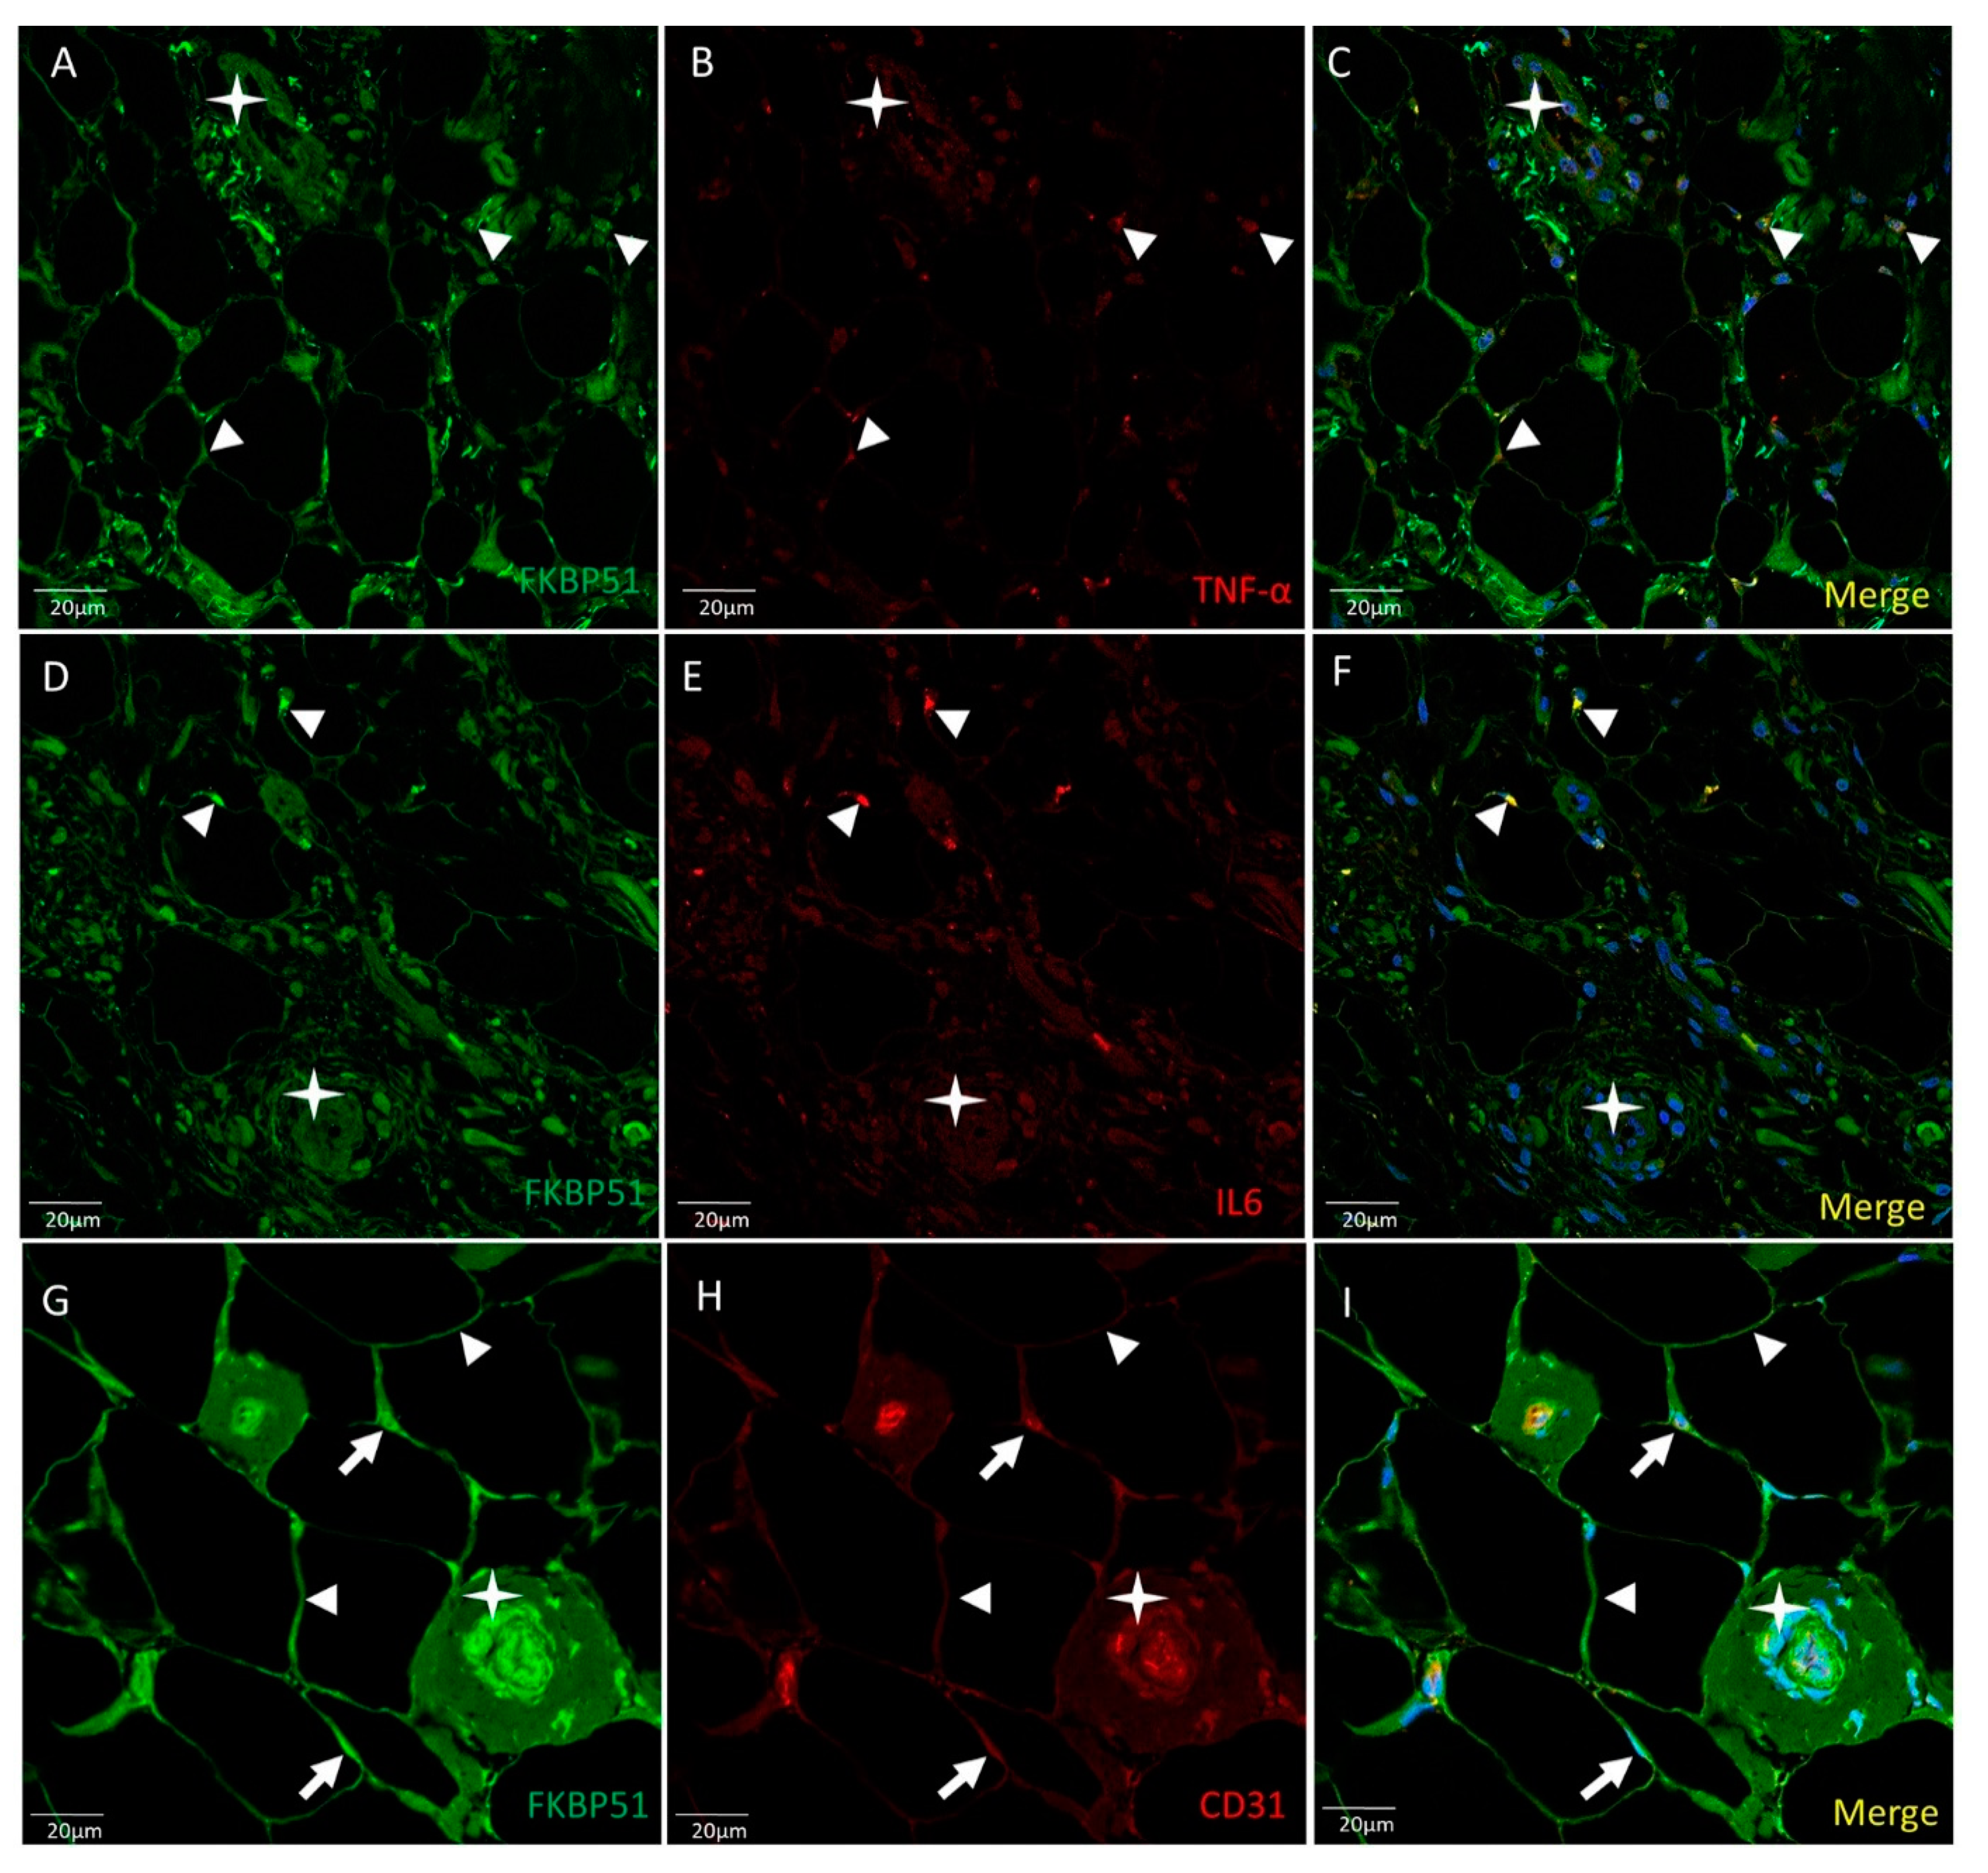

3. Results

4. Discussion